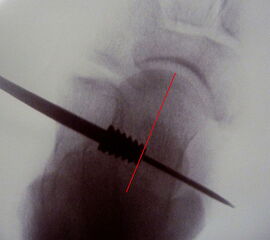

Abbildung 1

• ProStop Implantationssieb von Arthrex mit Führungspin, Probeimplantaten in aufsteigender Größe und lasermarkiertem Eindrehinstrument mit Handgriff (Abb.1).